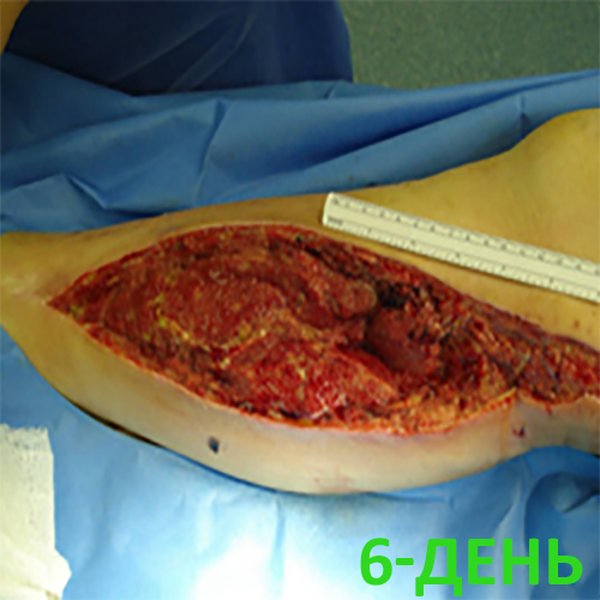

6-День лечения. Оценка состояния раны: Умеренная экссудация.

Размер раны: 8 х 38 см

Глубина раны: 2 см. Появляются грануляции.Перевязка: Рана обработана р-ром антисептика. Выполнена хирургическая обработка раны

Супрасорб CNP в постоянном режиме (-80 mmHg).